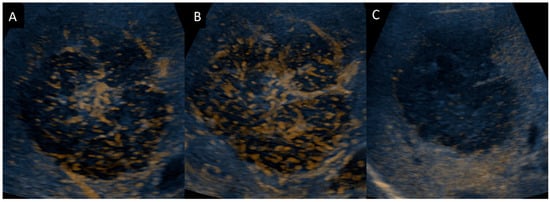

- Trenker, C.; Kunsch, S.; Michl, P.; Wissniowski, T.T.; Goerg, K.; Goerg, C. Contrast-Enhanced Ultrasound (CEUS) in Hepatic Lymphoma: Retrospective Evaluation in 38 Cases. Ultraschall Med. 2014, 35, 142–148. [Google Scholar] [CrossRef] [PubMed]